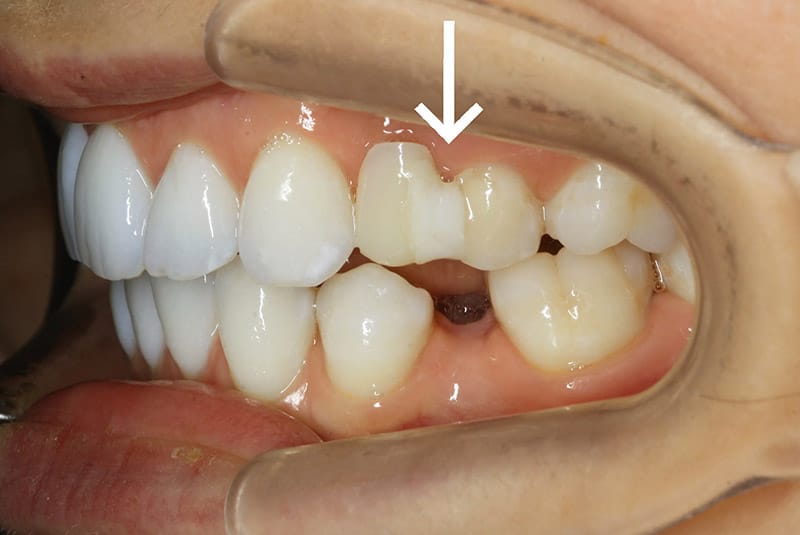

Bagues linguales outlet

Bagues linguales outlet, L orthodontie invisible pour les adolescents enfin une realite outlet

Orthodontiste Val de Marne 94 Interview d un patient avec beance outlet, Ma chirurgie Maxillo faciale Vlog 7 Appareil dentaire lingual temoignage outlet, Appareil Dentaire Adulte bagues lingual invisible Orthodontie Adulte outlet, Orthodontiste Paris Orthodontie linguale Paris outlet, L orthodontie invisible pour les adolescents enfin une realite outlet, Gouttieres invisibles ou bagues quelle solution choisir outlet, Bagues linguales hotsell ou invisalign outlet, L orthodontie invisible pour les adolescents enfin une realite outlet, orthodontie linguale Win specialite du cabinet du Dr Chassaing outlet, Lingual Braces The Dental Chambers Kensington outlet, Orthodontie adulte Dentiste Tremblay en France 93 outlet, Orthodontie Linguale a Paris Dr Issembert Orthodontiste outlet, Gouttieres invisibles ou bagues quelle solution choisir outlet, L orthodontie invisible pour les adolescents enfin une realite outlet, Appareil dentaire lingual pour les adulte Appareil Dentaire outlet, Orthodontie adulte outlet, Orthodontiste Val de Marne 94 Etapes de l Orthodontie Linguale outlet, Bagues linguales Orthodontie Lancy outlet, Bagues linguales ORTHODONTIE GARLABAN outlet, Orthodontie linguale finies les bagues apparentes outlet, Lingual Dr Soubrie Orthodontiste Voisins le Bretonneux Orthodontie 78 outlet, FAQ Quels sont les avantages et les inconvenients de l orthodontie linguale outlet, L orthodontie linguale SFODF outlet, Centre medico dentaire Blaise Pascal Dentiste a Trappes outlet, L essentiel sur les attaches linguales Centre dentaire des Tilleuls outlet, Orthodontie linguale Orthodontiste a Bordeaux Dr Francois Darque chirurgien dentiste outlet, Orthodontie Linguale toutes les infos a savoir Orthodontie Adulte outlet, Le traitement orthodontique lingual un appareil orthodontique totalement invisible outlet, Bagues et orthodontie le guide sur les differentes techniques outlet, Orthodontie Linguale Paris appareil dentaire lingual outlet, Orthodontie Linguale a Paris Dr Issembert Orthodontiste outlet, Les bagues et l orthodontie 3 grandes categories d appareils dentaires outlet, Lingual Orthodontics by Dr. Issembert Orthodontist outlet, Appareil dentaire invisible lingual Dr Ohana Chpindel outlet, Bagues linguales Orthodontie Lancy outlet, Product Info: Bagues linguales outlet.